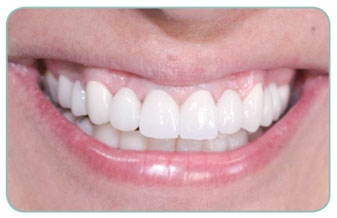

Our patient has now a hollywood stile smile after application of teeth whitening and four composit laminate veneers to fill the gaps between her teeth. During the treatment none of the teeth got a single damage.